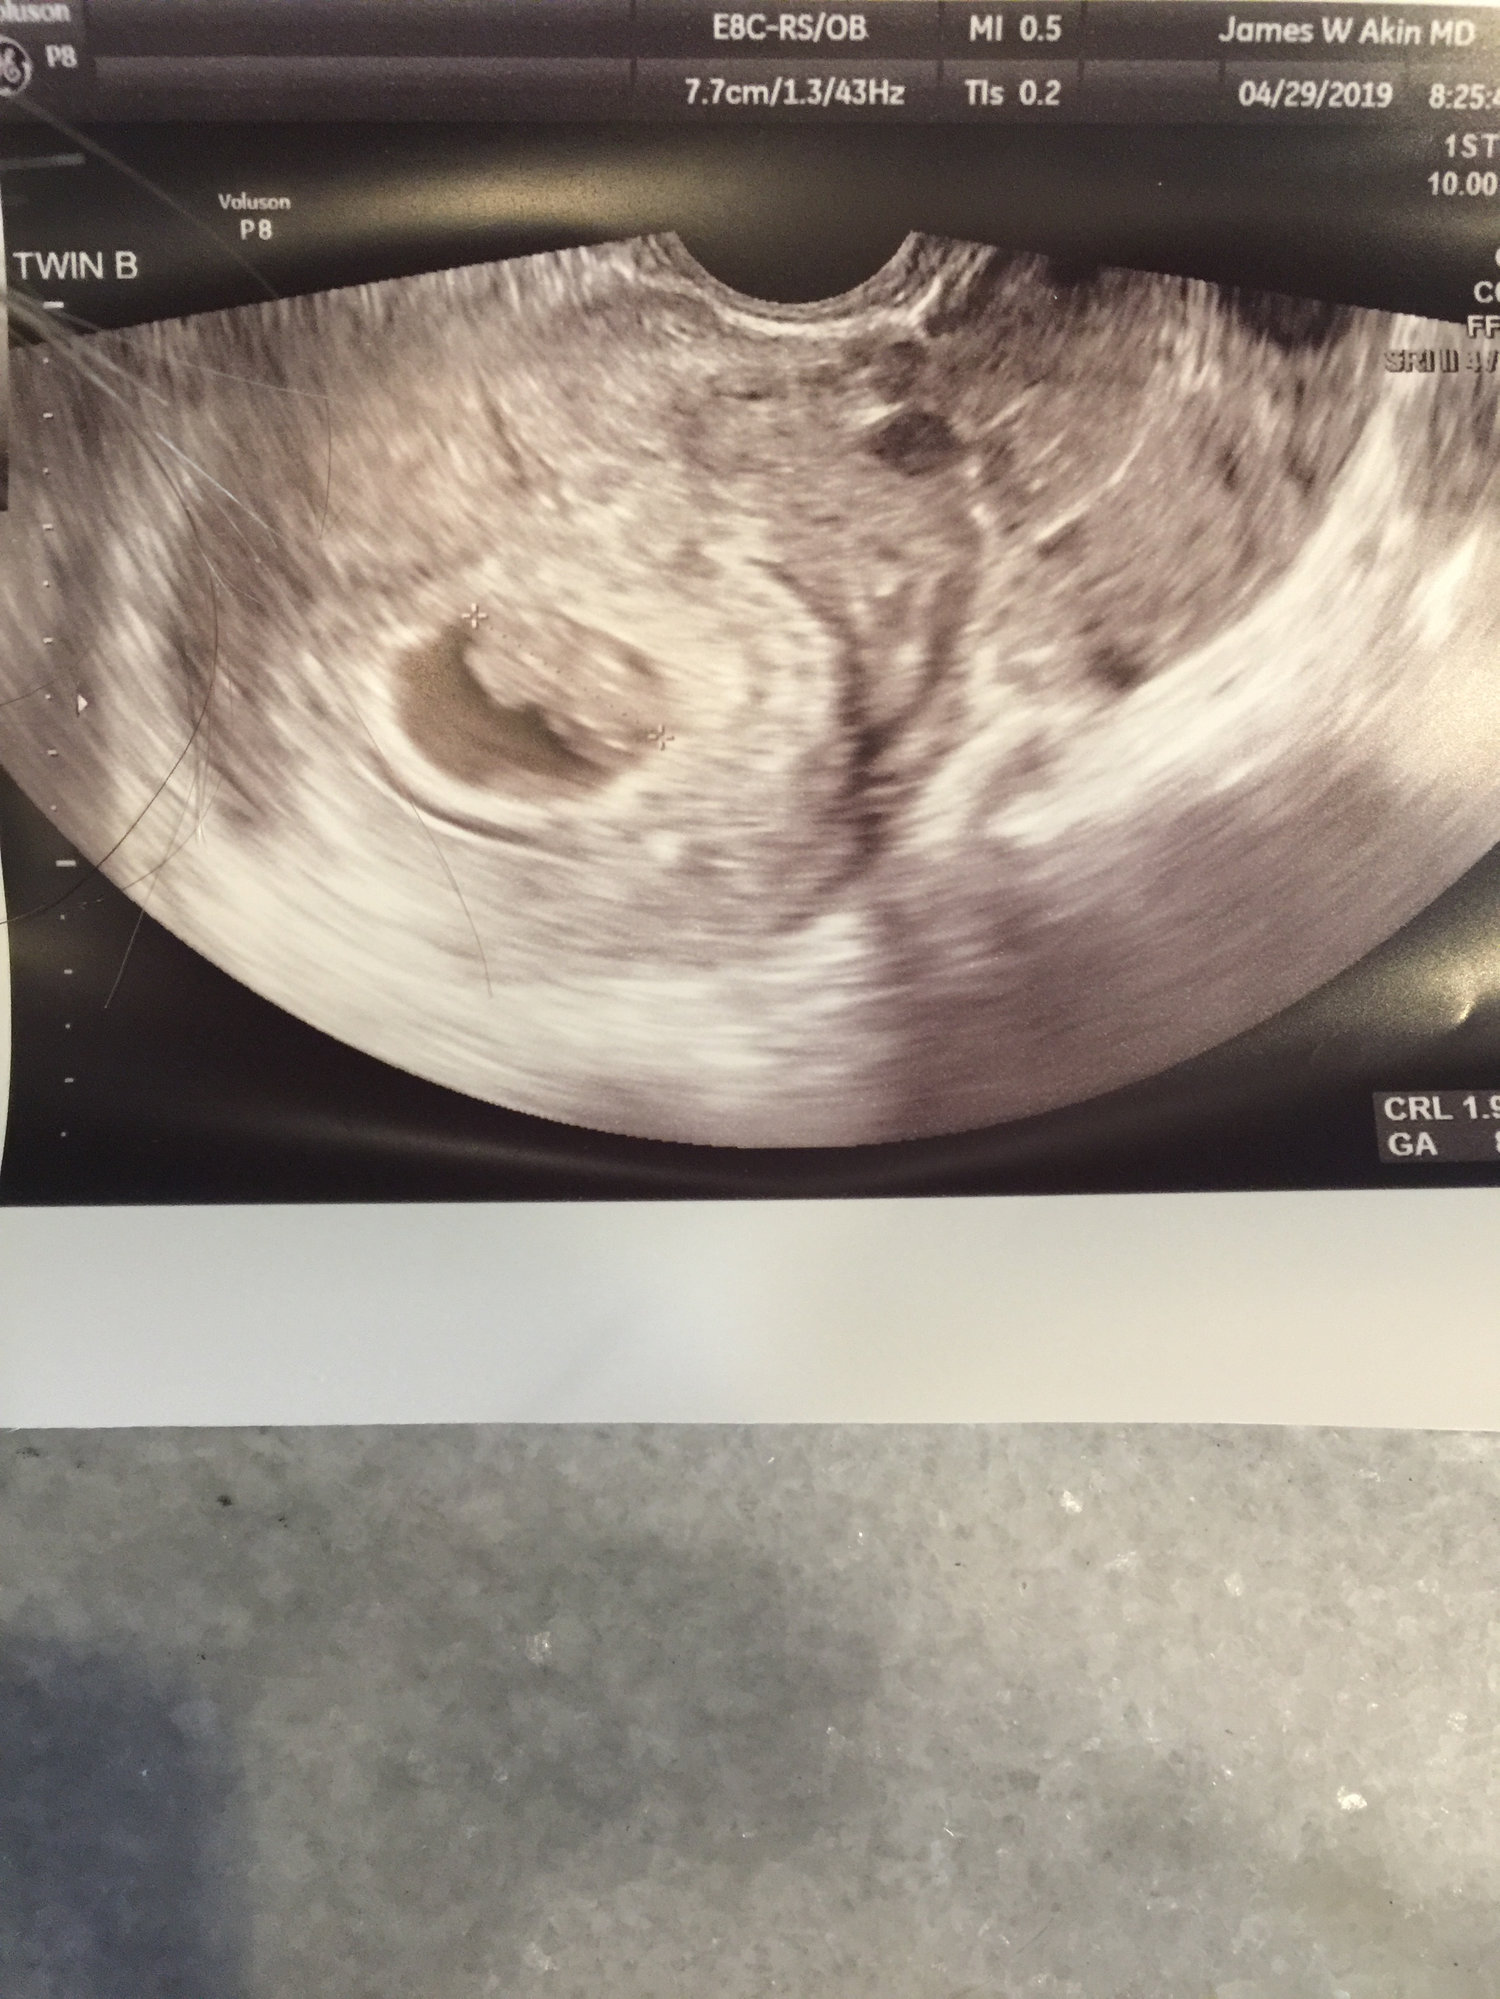

Found out yesterday, I am having twins.. EDD 12.7.19

6w2d EDD 12/18!! HR 112